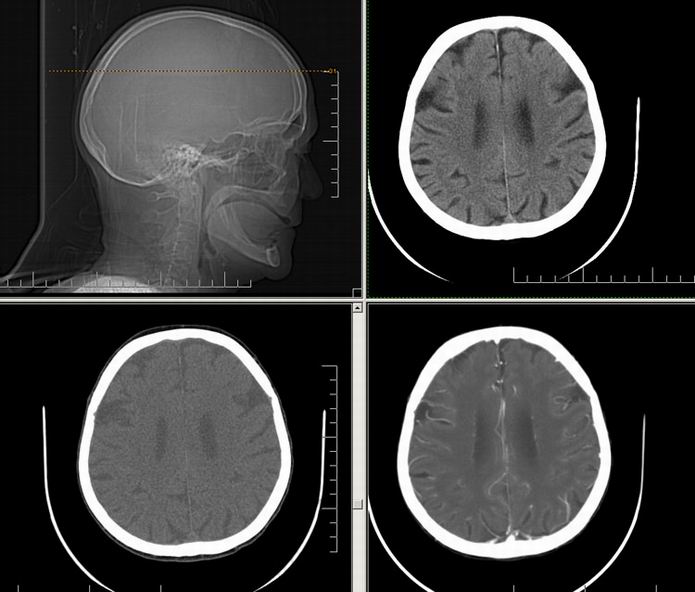

Est ce que qqun a des coupes axiales de crâne pour m'aider à réviser mon anatomie. Merci

Pour compléter tes révisions, Poupette vient de nous faire parvenir ces planches bien utiles: Planches de coupes axiales cérébrales, dans la rubrique COURS / ANATOMIE